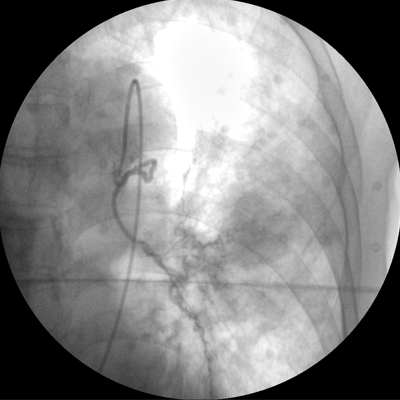

數(shù)字高清影像  助力臨床診斷

專業(yè)的圖像處理系統(tǒng),為您提供高分辨率、高灰階圖像。

Clinical picture

臨床圖片